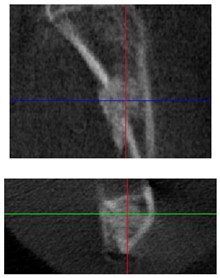

| Figurative Point | |||

|---|---|---|---|

| 3 | 5 | 8 | |

| 3D model and orthogonal projections Initial | ![]() | ![]() | ![]() |

![]() | ![]() | ![]() | |

| 3D model and orthogonal projectionsAfter implantation period of 3 months | ![]() | ![]() | ![]() |